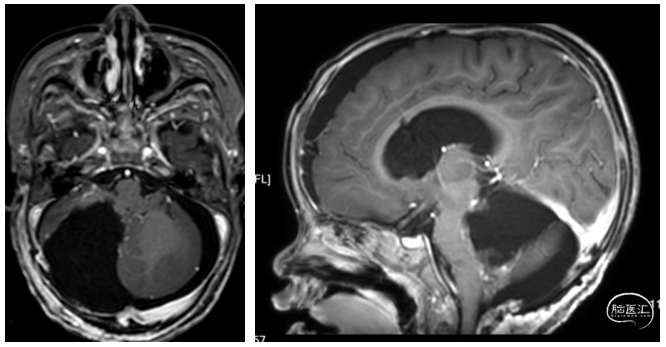

辅助检查: CT/MRI:右侧小脑半球-四脑室区占位,考虑肿瘤性病变,伴枕骨大孔疝、幕上重度脑积水伴脑室旁间质性水肿。

术前影像学

1.该肿瘤为一种特殊类型的髓母细胞瘤,作为小儿神经外科医生,应该对此有所了解,是一个手术前应该可以知道大体病理、分子分型和临床预后的肿瘤;患儿的CT/MRI会有特殊的临床表现,CT为高密度,MRI强化明显,而且呈现一种特殊的“葡萄样”形态。该“葡萄样”形态,是这种髓母细胞瘤的特色表现。手术后病理和分子分型也证实了我们的判断。